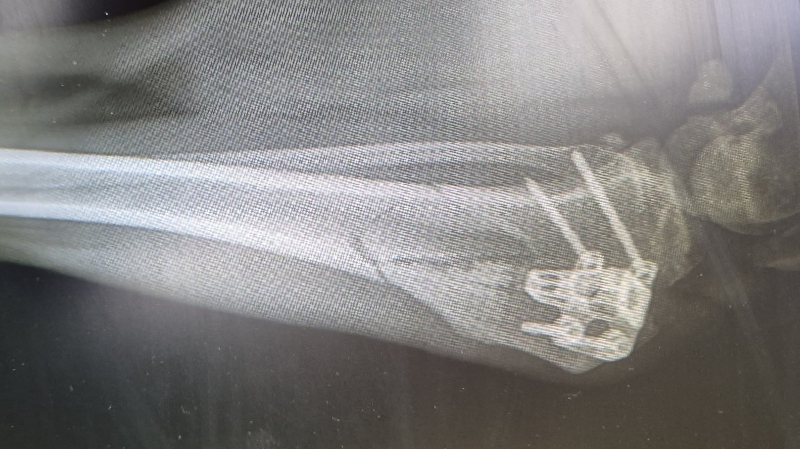

Nora hatte letztes Jahr einen Kreuzbandriss gehabt, sie wurde operiert. Leider hat sie sich 2 wochen (26.05.25) später das operierte Bein gebrochen.

ca 3 Wochen später musste sie wieder operiert werden weil der Draht aus dem Bein kam.

Nora wird am 21.01.26 wieder operiert da ein teil der Inplantate raus genommen wird.